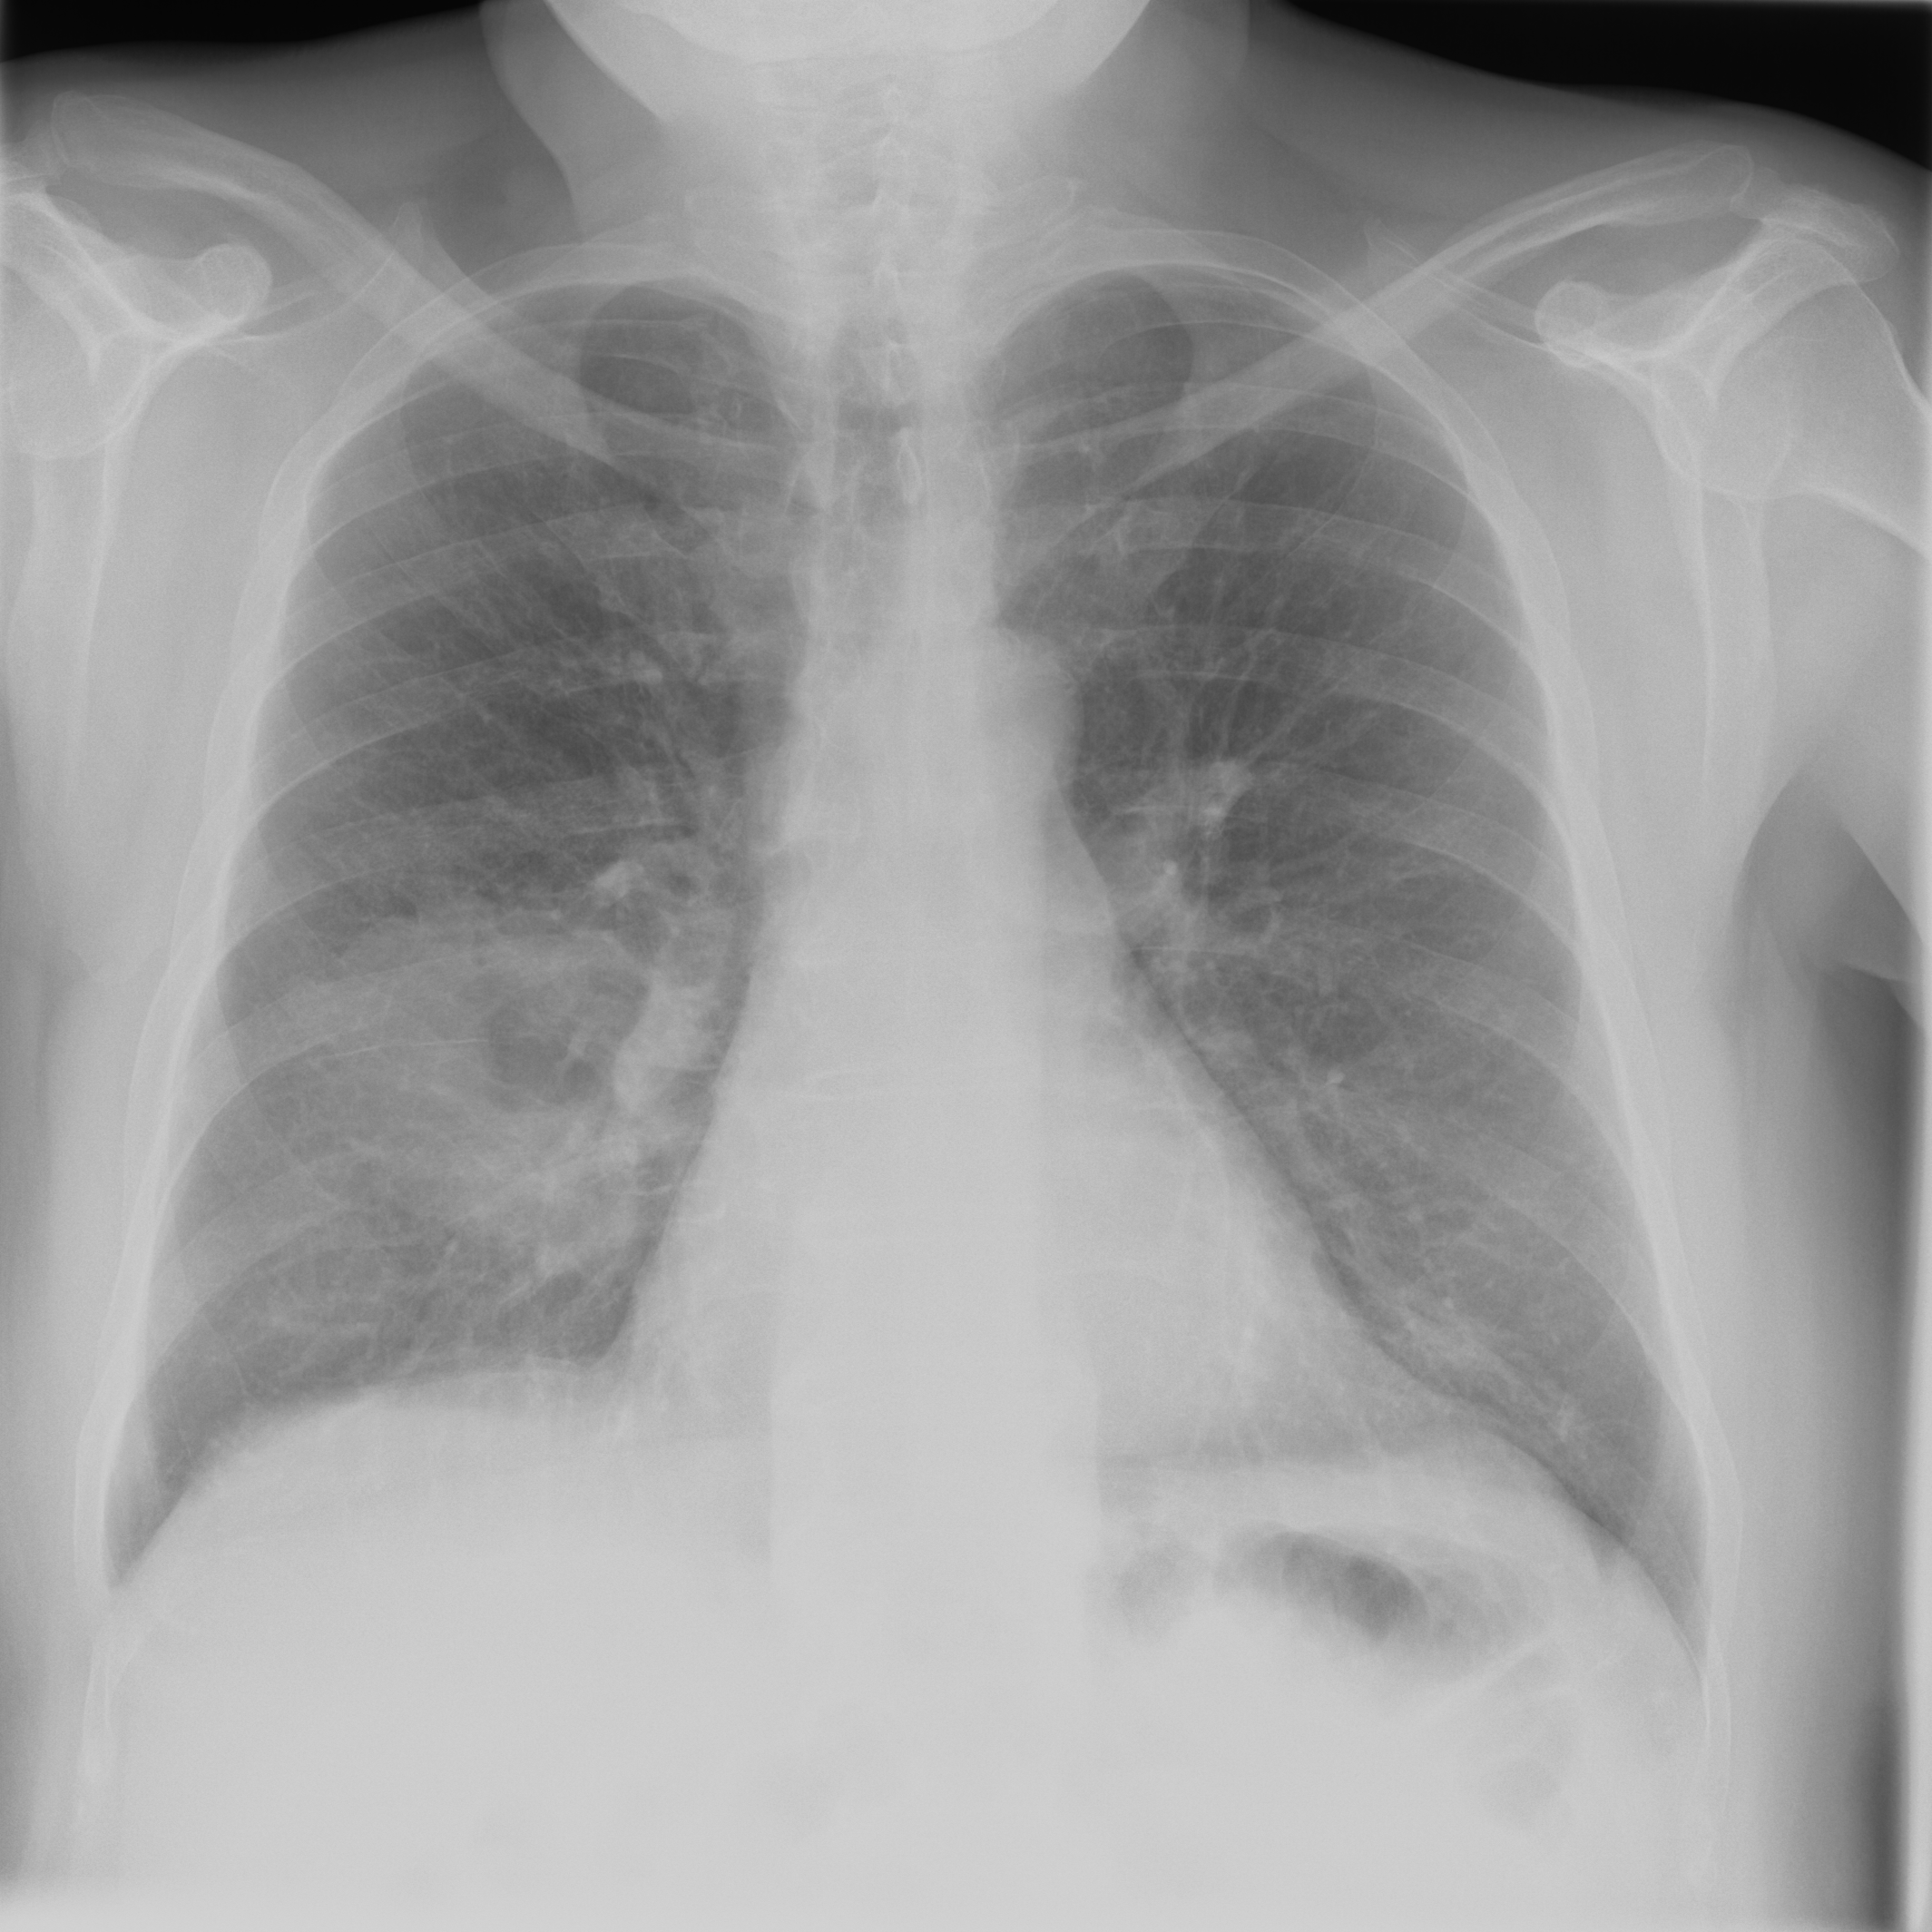

3.3 X-Ray

X-ray imaging is a fundamental form of radiography. Reducing radiation dose while maintaining image quality is a key principle in radiology known as ALARA (As Low As Reasonably Achievable) (citep \@BBN(Schiska, 2021)). New technologies and imaging techniques, such as post-processing by artificial intelligence (AI) (citep \@BBN(Harvey and Topol, 2020)), may allow diagnostic objectives to be achieved with lower radiation doses. Furthermore, advancements in X-ray have also the potential to influence and enhance Computed Tomography (CT) (citep \@BBN(Feghali et al., 2021)). Whereas CT requires complex imaging reconstruction algorithms, X-ray is more straightforward, employing post-processing for high-quality and detailed imaging. This is crucial for clinical assessment of anatomical structures and potential pathologies, being often used to guide treatment decisions and to plan interventions, such as surgery or radiotherapy.

3.3.1 Post-processing problem

The raw data captured during digital radiography reflects the pattern of X-ray attenuation by different tissues. The digital signal is then processed to create a greyscale image, where each shade corresponds to the radiodensity of the tissues, ranging from black for air through varying shades of grey for soft tissue and white for bone. Post-processing software refines the raw image to enhance clarity and diagnostic utility (citep \@BBN(Seeram and Seeram, 2008)). This may involve adjusting parameters such as brightness and contrast, applying filters for noise reduction, or using algorithms for edge enhancement (citep \@BBN(Krupinski et al., 2007)). The aim is to produce an image that provides the best possible diagnostic information while adhering to the ALARA principle.

Different quality properties may be desired depending on the purpose of the X-ray. For example, when visualizing the lung tissue, adjustments are made to the brightness and contrast to best highlight the anatomy and common abnormalities whilst minimizing noise. However, noise is less important when aiming to confirm the position of a line, tube, or foreign object. In this case, an image with edge enhancement and adjusted brightness levels may be desirable to amplify the distinction between the dense material of the object and the surrounding soft tissue.

Quality control for the provided default post-processing is usually made by the manufacturers themselves, therefore not accessible to the end user, and may be divergent to the IQ needed for clinical images (citep \@BBN(Tsalafoutas et al., 2024)). After the machine has been placed in the hospital environment, personalized post-processing settings are often determined by subjective visual inspection. Objective evaluation would help to find an optimal post-processing type for visualization, allowing faster and consistent evaluation. Beyond this setting, objective IQA is important for the development and testing of machine learning algorithms on chest X-ray images including super-resolution, denoising or inpainting methods, where PSNR and SSIM are currently the standard choice for quality assessment, see e.g. (citep \@BBN(Tran et al., 2021; Mandić et al., 2018; Wang et al., 2021; Thanh et al., 2020; Jiang et al., 2021)).

3.3.2 Data

Posteroanterior chest radiographs were acquired on two imaging systems (both Discovery XR656 HD models, GE Healthcare, USA) at Cambridge University Hospitals NHS Trust. Each scanner was being set up in the hospital with different post-processing parameters (chosen by the operating radiologists), which are used here as reference images, see Figure 7 and 8(a). Additional images, serving as real-life examples of lower quality, were produced for each radiographic exposure using multiple different post-processing settings. The post-processing was applied in the hospital directly on the scanner itself by adjusting parameters in the provided framework.

Refer to caption

(a) Reference

(b) (21.1, 0.90, 0.11)

(c) (19.5, 0.88, 0.16)

Figure 7: Chest X-Ray scans with different kinds of post-processing; (a) serves as reference and (b) is wrongly judged as better visualization by PSNR/SSIM/LPIPS.

(b) (22.8, 0.97, 0.08)

(c) (21.2, 0.96, 0.07)

Figure 8: Chest X-Ray scans with different kinds of post-processing; (a) serves as reference, (b) is wrongly judged as better visualization by PSNR and SSIM, LPIPS gives a slightly worse evaluation for (b).

In Figure 7, contrast deviation and edge enhancement were reduced in (b), but increased in (c), the noise reduction algorithm was removed in both. The brightness was increased in both images but more so in (c) and low-contrast enhancement was removed in (b). The result is that (b) has relatively low contrast in the lungs compared to the reference (a) and radiograph (c). In Figure 8, edge enhancement has been dramatically increased in (b), whilst the contrast deviation and tissue contrast have been reduced. In (c), the brightness, tissue contrast and edge enhancement have been slightly increased. Consequently, (b) provides low contrast in the lungs with excessively prominent lung markings and vasculature which make it harder to detect abnormalities such as a pneumonia.

FR-IQA mismatches

In Figure 7 and 8 we apply the standard FR-IQA metrics to the images with diverging quality. Although it is visually obvious that image (b) has lower visual quality, it is judged wrongly as the better image by all measures in the first example Figure 7, and the results in (b) and (c) of the second example Figure 8 are quite close, where PSNR and SSIM are also providing the wrong order. This indicates that the tested standard FR metrics are not suitable to evaluate the quality of data sets with X-Ray images that have large variations regarding contrast, luminance and sharpness.